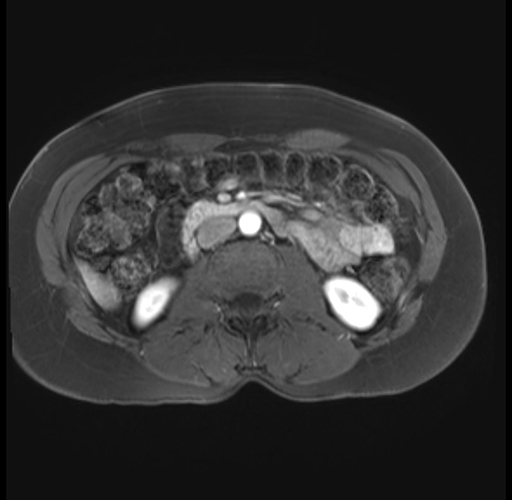

Imaging Analysis

Look through the patient's CT scan to identify any areas of concern for the necessary procedure.

Based on your CT findings, which issue(s) are present and would give reason for "planned slowing down moment(s)" in this case?